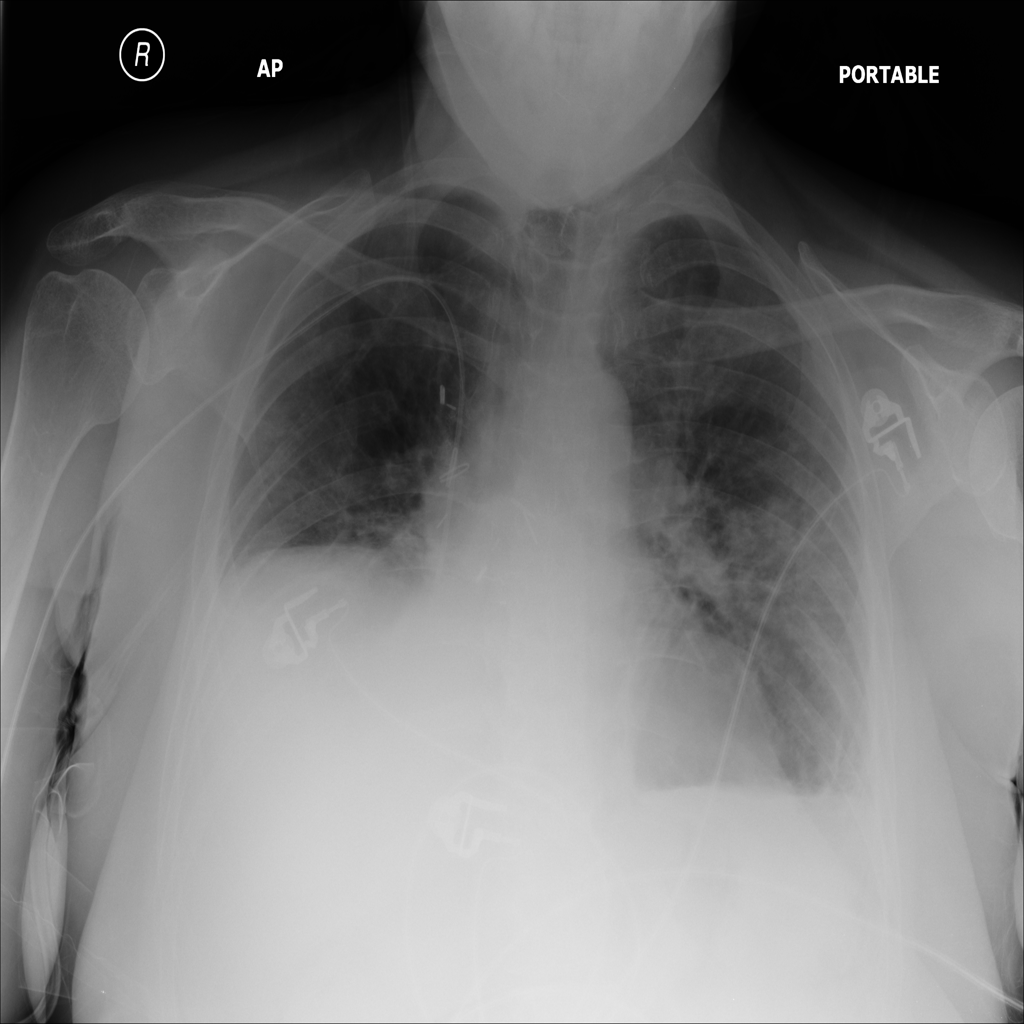

PAT-E81B · IMG-000Effusion

PAT-E81B · IMG-000

PA